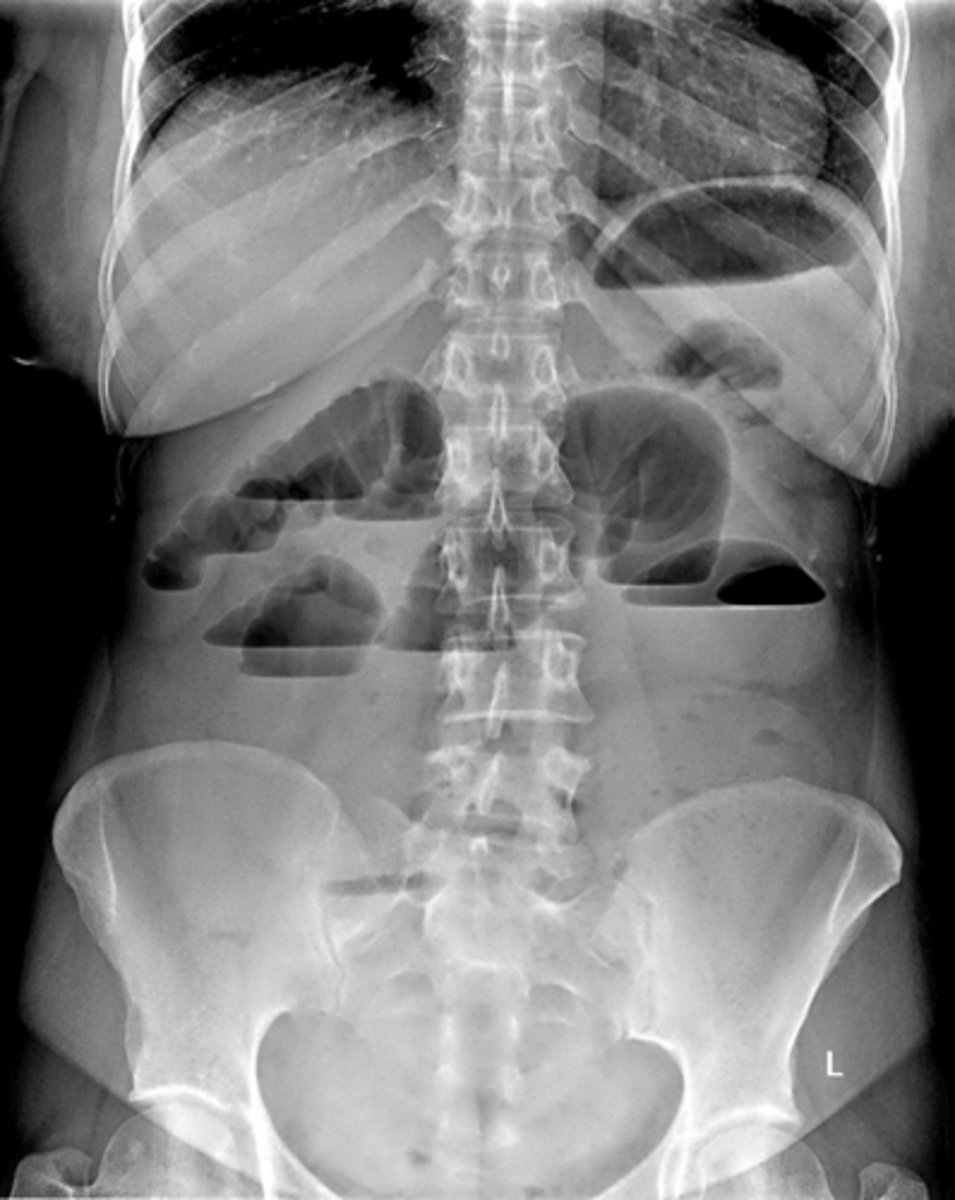

Air fluid levels due to small bowel obstruction (SBO)

air fluid levels

caused by intestinal obstruction, prevents flow of fluids and gas, appears like a turtle shell

bowel dilation

caused by mechanical obstruction or impaired bowel motility, looks like a slinky

loops ____ to obstruction become dilated with air and fluid. Loops ____ to obstruction become decompressed as their contents are evacuated

proximal, distal

small bowel obstruction usually starts in the ______

LUQ

causes of SBO

post-operative adhesions, malignancy, hernias, gallstone ileus, intussusception, IBD

string of pearls sign- diagnostic of mechanical obstruction

stretch sign- small pockets of gas trapped bn valvulae conniventes within fluid filled bowel